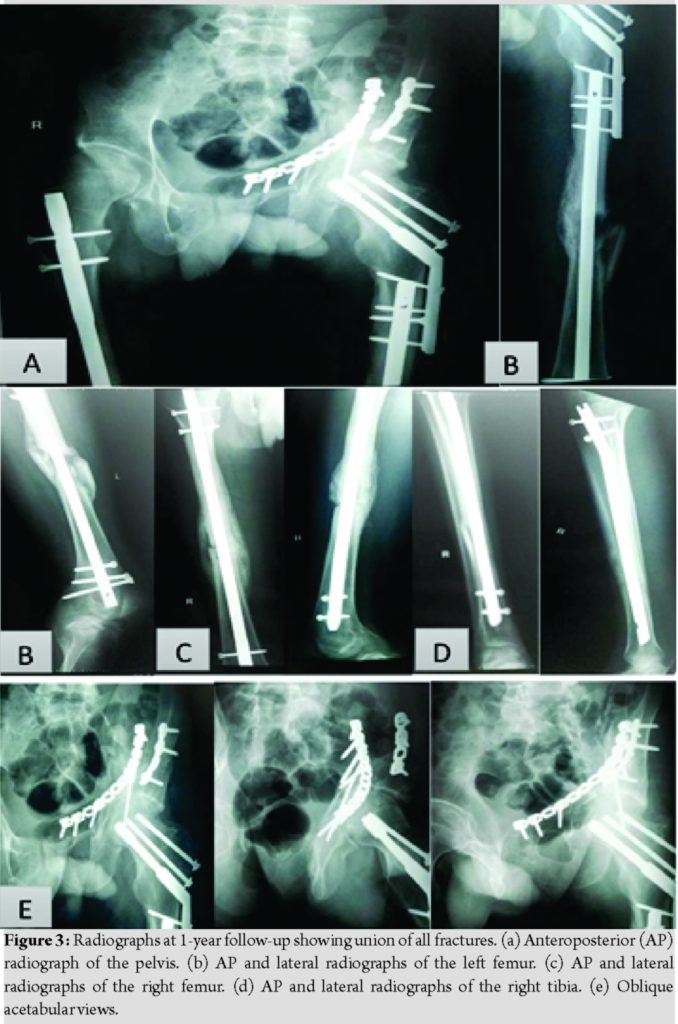

The early post-operative period passed uneventfully. Passive and active hip and knee range of motion (ROM) was allowed after each operation as tolerated, sutures were removed 2 weeks after the operation and all wounds healed uneventfully. In the 8th post-operative week, partial weight-bearing was allowed on two crutches, Harris hip score (HHS) of the left hip was 75, callus formation started to appear at the shaft femurs and the shaft tibia, and both knees achieved full active and passive ROM without significant knee pain. In the 12th post-operative week, partial weight-bearing was continued, and HHS of the left hip increased to 80. In the 16th post-operative week, all fractures were fully united, full weight-bearing was allowed and the HHS was 90. The remaining follow-up period was uneventful, and at 1 year, HHS of the left hip reached 95, in addition, both knees achieved full ROM without knee pain (Fig. 3).